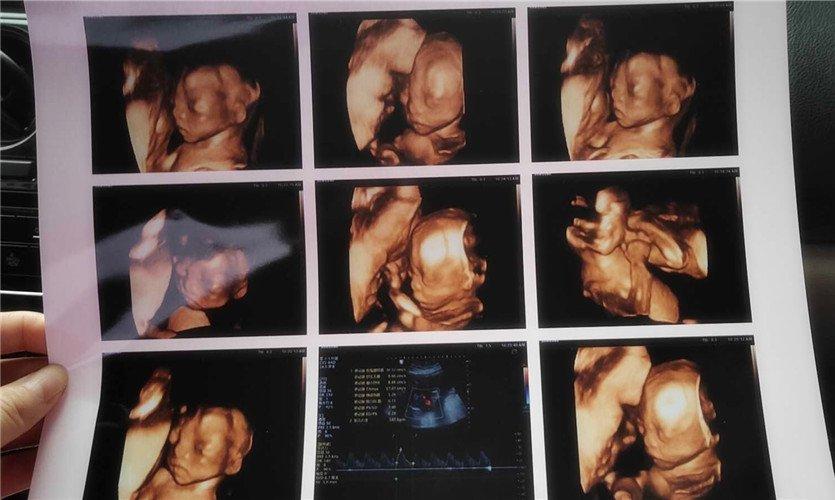

四維彩超是一種先進(jìn)的醫(yī)學(xué)影像技術(shù),通過實時觀察胎兒在母體內(nèi)的活動情況,為醫(yī)生提供了豐富的診斷信息,在四維彩超下,我們可以清晰地觀察到胎兒的蛋蛋(睪丸)的形態(tài)、位置和大小等特征,胎兒蛋蛋是男性生殖系統(tǒng)的重要組成部分,對于胎兒的生長發(fā)育具有重要意義。

在四維彩超下,胎兒蛋蛋呈現(xiàn)出特定的形態(tài)和外觀,通常情況下,胎兒蛋蛋呈現(xiàn)出圓形或橢圓形,表面光滑,內(nèi)部回聲均勻,隨著胎兒的發(fā)育,蛋蛋會逐漸增大,并呈現(xiàn)出明顯的性別特征,醫(yī)生可以通過四維彩超技術(shù),對胎兒蛋蛋的大小、形態(tài)和位置進(jìn)行評估,以判斷胎兒生殖系統(tǒng)的健康狀況。

胎兒蛋蛋的發(fā)育是一個復(fù)雜的過程,受到多種因素的影響,在胎兒發(fā)育的早期階段,蛋蛋位于腹腔內(nèi),隨著胎兒的生長發(fā)育,蛋蛋逐漸下降至陰囊,這個過程受到激素、遺傳和環(huán)境等多種因素的影響,在四維彩超的觀測下,我們可以實時了解胎兒蛋蛋的發(fā)育過程,及時發(fā)現(xiàn)異常情況并采取相應(yīng)的治療措施。

四維彩超技術(shù)在評估胎兒蛋蛋發(fā)育方面具有重要意義,通過四維彩超,醫(yī)生可以實時觀察胎兒蛋蛋的形態(tài)、位置和大小等特征,了解胎兒生殖系統(tǒng)的發(fā)育情況,四維彩超還可以幫助醫(yī)生發(fā)現(xiàn)可能的異常情況,如睪丸未降、睪丸囊腫等,為及時采取治療措施提供依據(jù)。